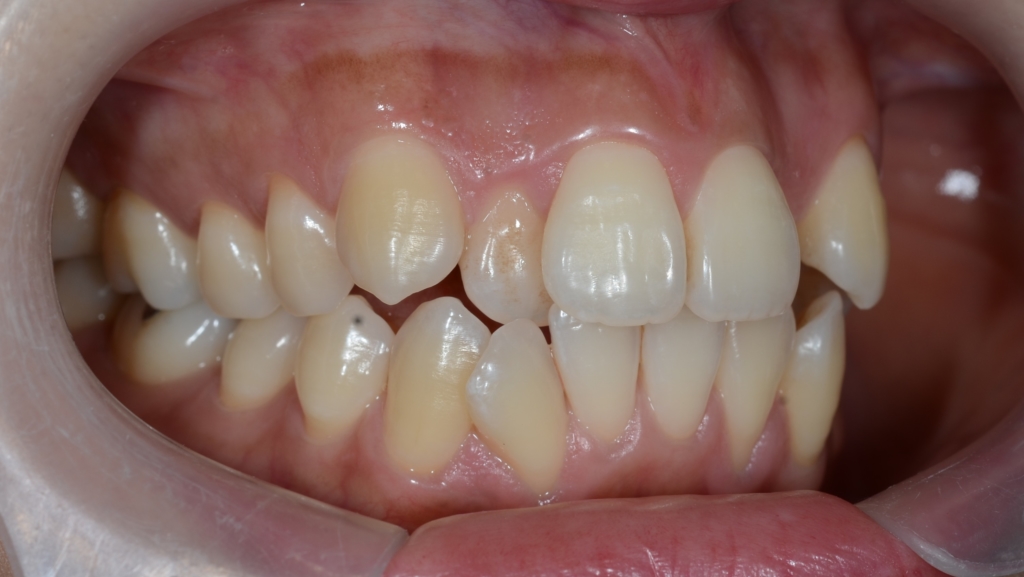

【Before】

#1.顎と歯の不調和による叢生(重度)

#2.上顎前突(奥歯の噛み合わせ)

と診断しました。